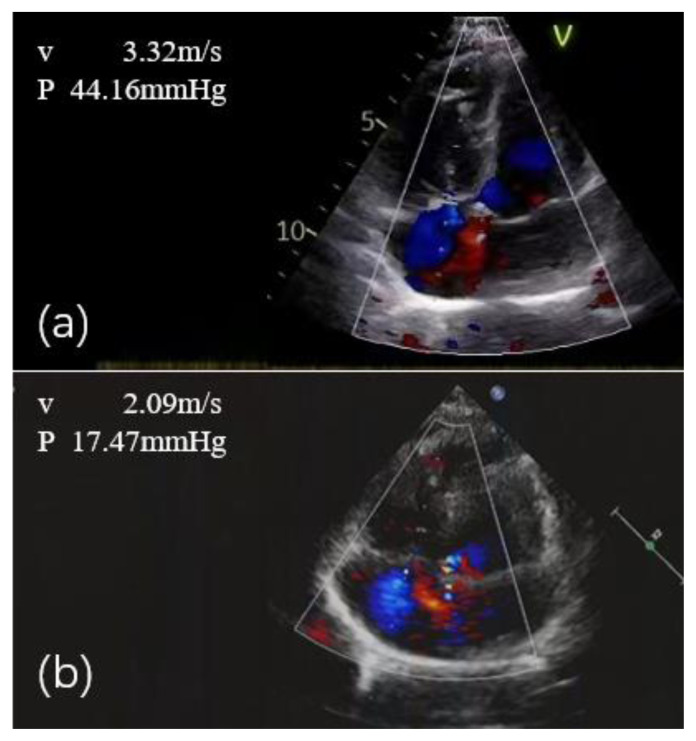

Luspatercept Treatment in a β-Thalassemia Patient with Pulmonary Arterial Hypertension: A Case Report.